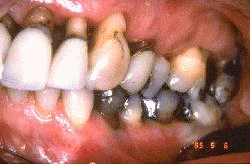

Mujer de 60 años de edad  que ha desarrollado  enfermedad periodontal severa. Las profundidades de las bolsas al sondaje son de 5 a 8 mm y el examen radiográfico muestran que aproximadamente 50%  del hueso alveolar se ha perdido en el maxilar  superior. Las encías superiores muestran signos de inflamación severa.  Los rasgos clínicos no permiten un análisis de la anatomía de la destrucción periodontal.